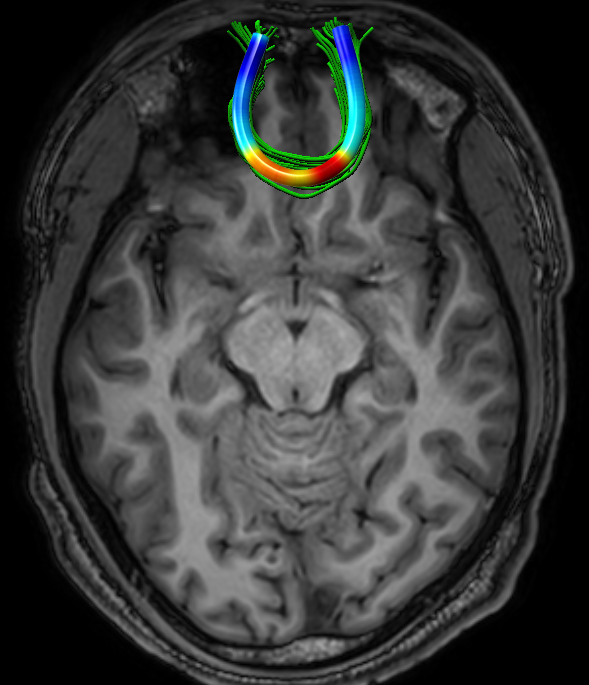

3.2 Football Players Study

We analyzed 13 active professional American-football players (mean age = 28.3, STD = 6.4), with respect to 17 NCs (mean age = 26.1, STD = 2.3). For each subject, four FFDD tract-profiles were computed (based on FA, MD, RD, and AD), for each of the five examined tracts. The standardized FFDD profiles of NCs are shown in Fig. 3. Note that although FFDD values vary along the tracts, their profiles are consistent across subjects.

Fig. 4 presents pointwise group-average and STD of MD-FFDD profiles of football players, demonstrating increased values at the occipital part of the left IFOF, and at the central part of the FMT, compared to NCs. Note that the football group also exhibits higher STD values compared to NCs, at the same areas along the tracts with increased group-average values. This statistical spread indicates that only a subset of the football players group has abnormal FFDD values, as expected.